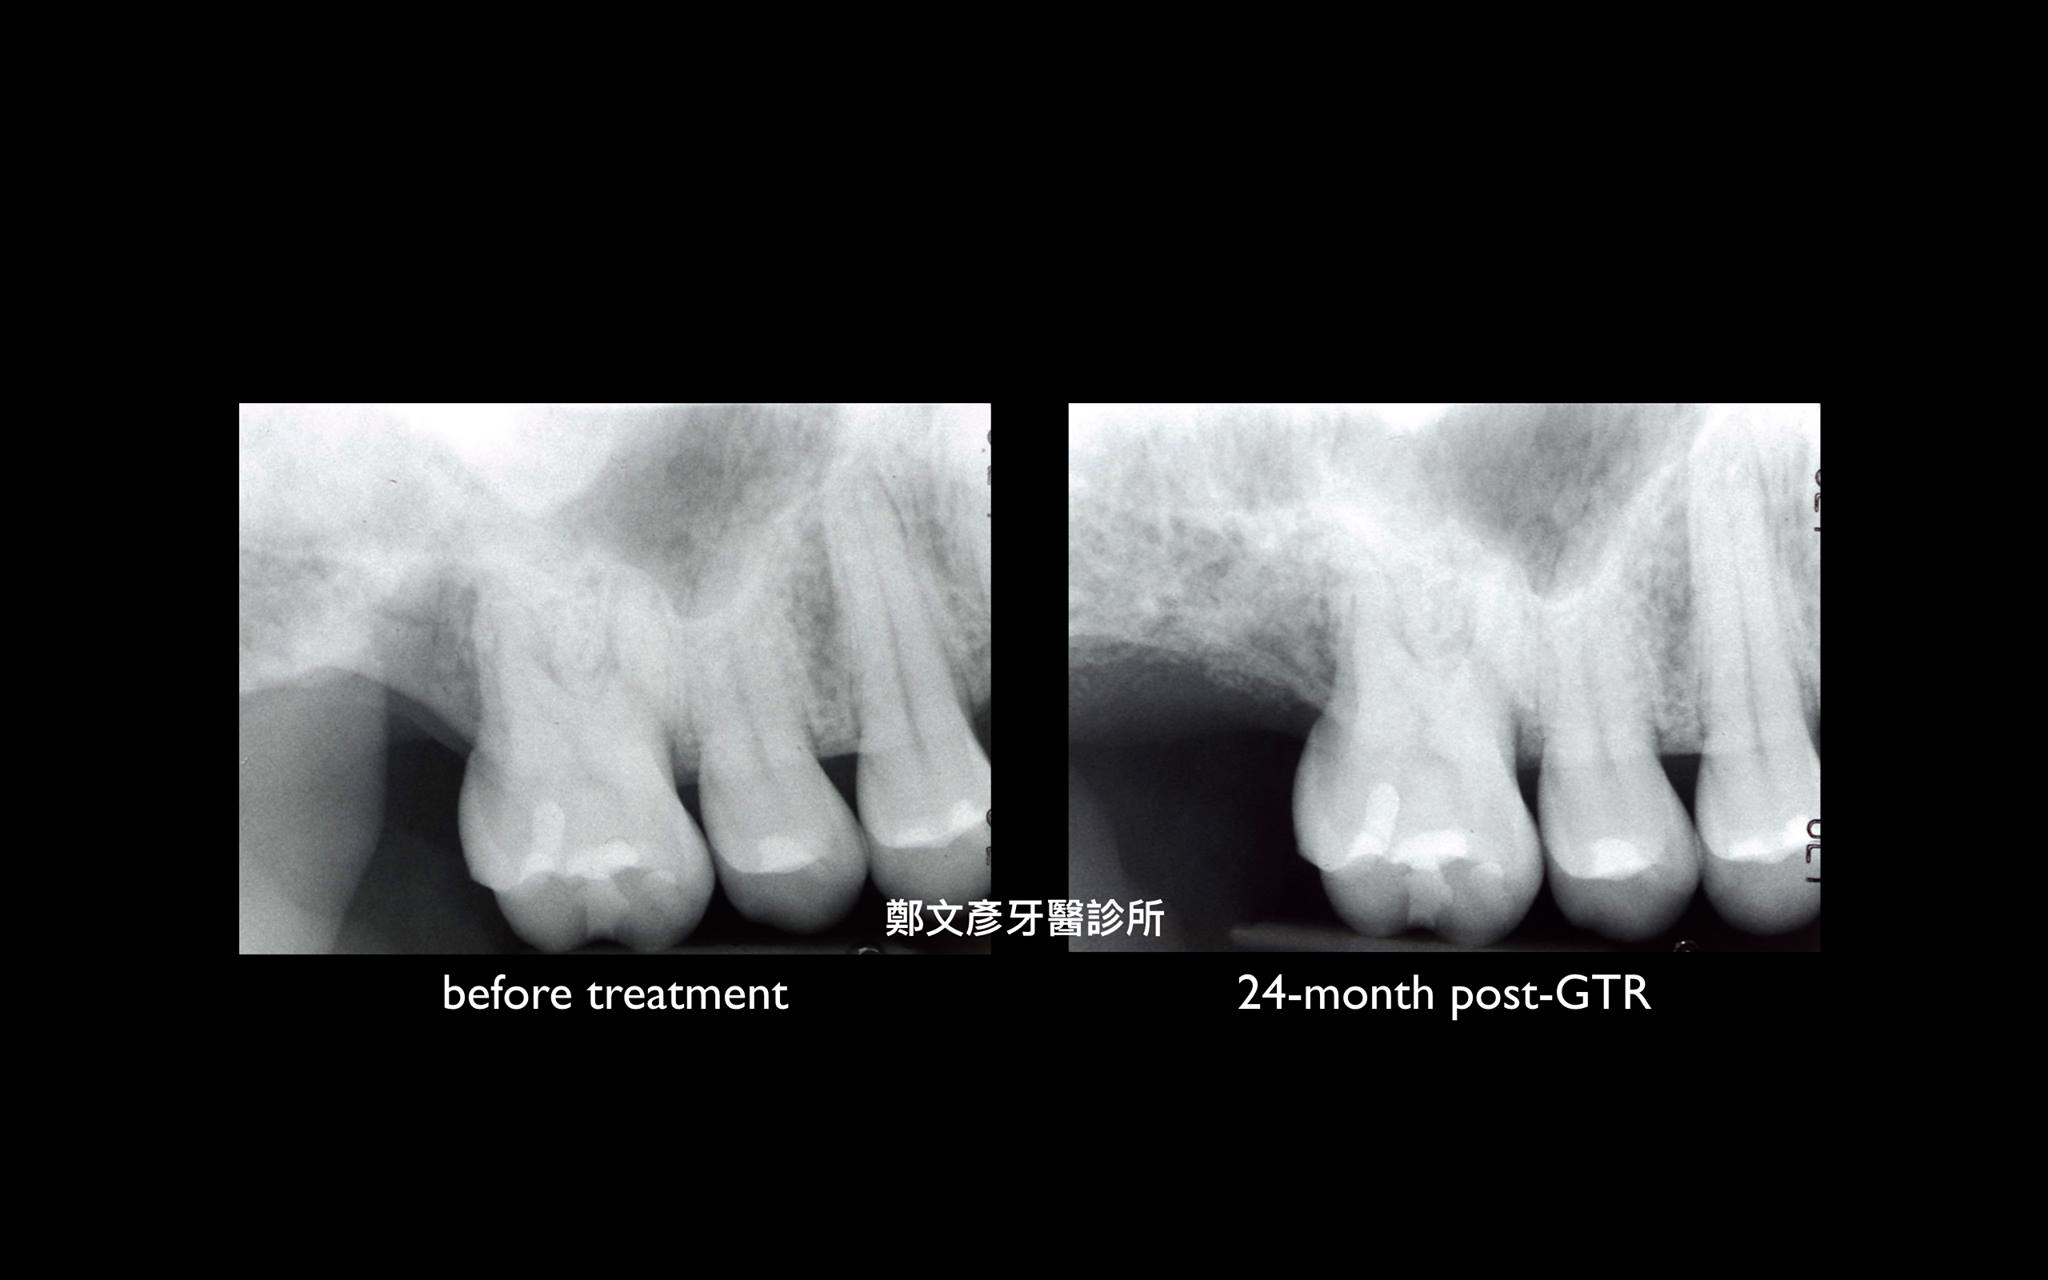

牙周再生補骨手術 ( GTR )

再生補骨